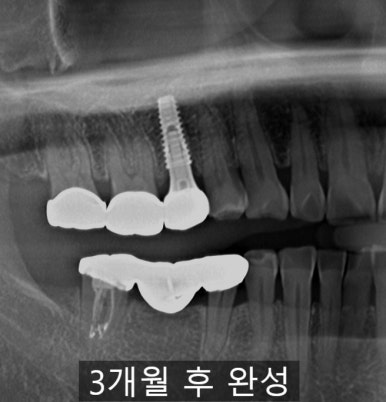

1️⃣ 즉시 식립(Immediate Implant)

즉시 식립은 이름 그대로

치아를 뽑은 당일, 같은 자리에서 임플란트를 심는 방법입니다.

- 발치와 식립을 한 번에 → 전체 치료 기간 단축